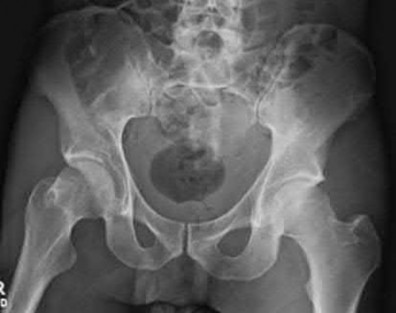

Question 1:

During an anterior intrapelvic (modified Stoppa) approach for the fixation of an acetabular fracture, the surgeon encounters significant bleeding from a vascular anastomosis situated over the superior pubic ramus. What two main vessels typically form this specific anastomosis (Corona Mortis)?

Correct Answer: Inferior epigastric artery and obturator artery

Explanation:

The corona mortis ('crown of death') is a vascular anastomosis between the external iliac and internal iliac vascular systems. Specifically, it connects the inferior epigastric artery or vein (from the external iliac system) to the obturator artery or vein (from the internal iliac system). It is located on the posterior aspect of the superior pubic ramus, approximately 4-7 cm from the pubic symphysis, and is at high risk of iatrogenic injury during the modified Stoppa or ilioinguinal approaches.